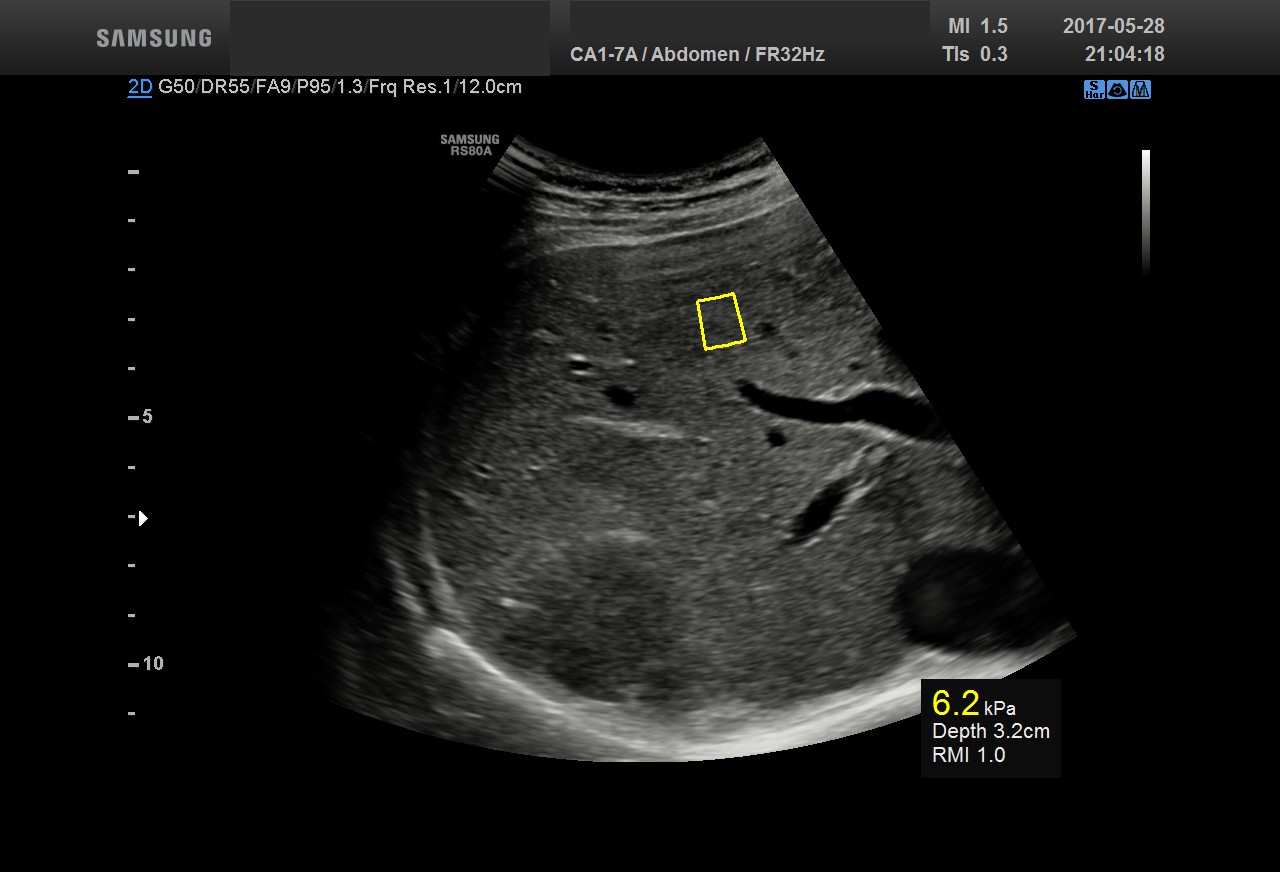

• USG jamy brzusznej

z oceną wątroby, trzustki, nerek, śledziony, pęcherza, gruczołu krokowego, dużych naczyń jamy brzusznej oraz przestrzeni okołoaortalnej.

• USG jamy brzusznej z oceną wątroby, trzustki, nerek, śledziony, pęcherza, gruczołu krokowego, dużych naczyń jamy brzusznej oraz przestrzeni okołoaortalnej

• zmian miąższowych wątroby

• oceny włóknienia wątroby (choroby wirusowe, marskość)

• ocena stłuszczenia wątroby

• diagnostyka NADCIŚNIENIA WROTNEGO - badanie śledziony

Badanie elastograficzne można wykonać w naszej pracowni jako rozszerzenie badania USG tarczycy i piersi (ocena guzków), a także jako samodzielne badanie – elastografia wątroby w celu oceny włóknienia(stosowana u nas metoda elastrografii 2D-SWE jest znacznie dokładniejsza od dotychczas stosowanej metody TE [FIBROSCAN®].